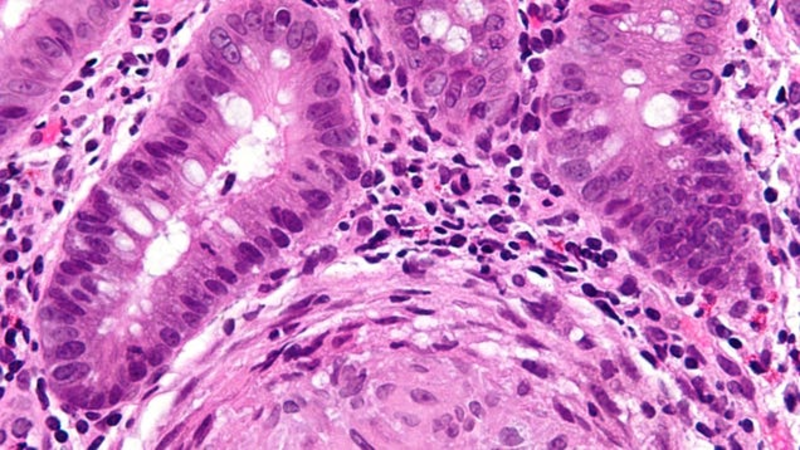

Researchers in the UK appear to have discovered a pivotal genetic cause of inflammatory bowel disease. In a new study Wednesday, the team found evidence of a specific genetic flaw that seems to play a key role in driving immune cells to attack the guts of those with IBD—a flaw found in nearly all the cases they…